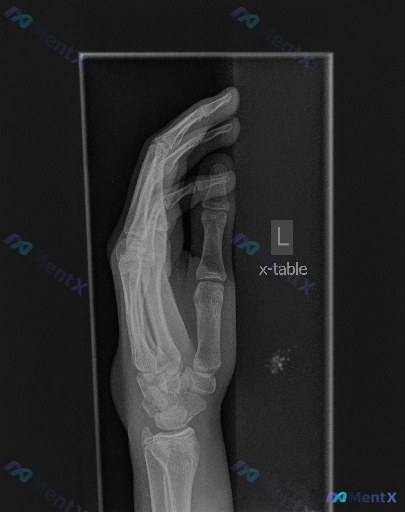

左手X线发现掌心软组织内高密度影,更倾向哪种原因?

大家好,今天我们来讨论一张左手的X线片。这是一张左手侧位/斜位投照的影像,曝光适中,骨皮质轮廓清晰。首先和大家同步一下影像的基础表现:

- 骨骼方面:第1-5掌骨、近中节指骨及可见腕骨区域,均未见明确的骨皮质中断、骨折线或关节脱位征象,骨骺线已闭合,各关节对位良好、间隙清晰,也未见明显的骨赘形成。

- 软组织方面:手掌及手指近端软组织轮廓尚自然,未见明显的弥漫性肿胀,但在掌心区域、拇指掌骨下方的软组织内,可见一处局限性的高密度影,边界尚清。

想请各位老师聊聊,单从这张影像的表现来看,你更倾向于哪一种初步判断方向?